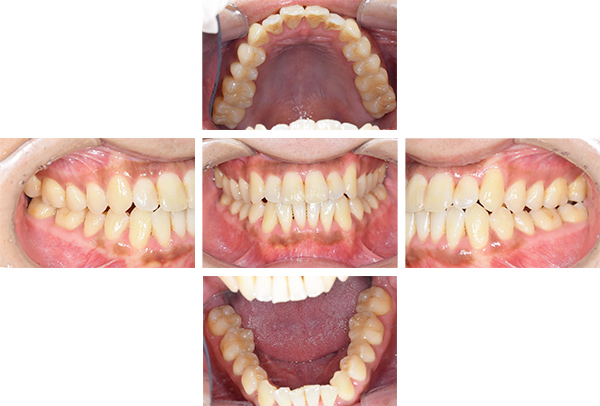

歯列矯正・インレー・クラウン症例

前歯が黒っぽいのが気になる、

悪いところは全部治したい

年齢 54代女性

主訴 歯をきれいにしたい

症例写真(治療前)

治療前:

八重歯が目立ちます。また銀歯もおおく、見た目が気になります。虫歯も散見できます。

レントゲン写真(治療前)

担当医師所見

根の治療を3本すでに治療されています。1本根の奥の詰め物が疎になっていますので、根の部分の再治療も行う必要がありそうです。銀歯の中で虫歯になっているものもあります。

症例写真(治療後)

治療後:

矯正治療と虫歯の治療すべて終わったときの写真になります。見た目も最初の頃とは全く違いますし、お口の中もすごく綺麗です。